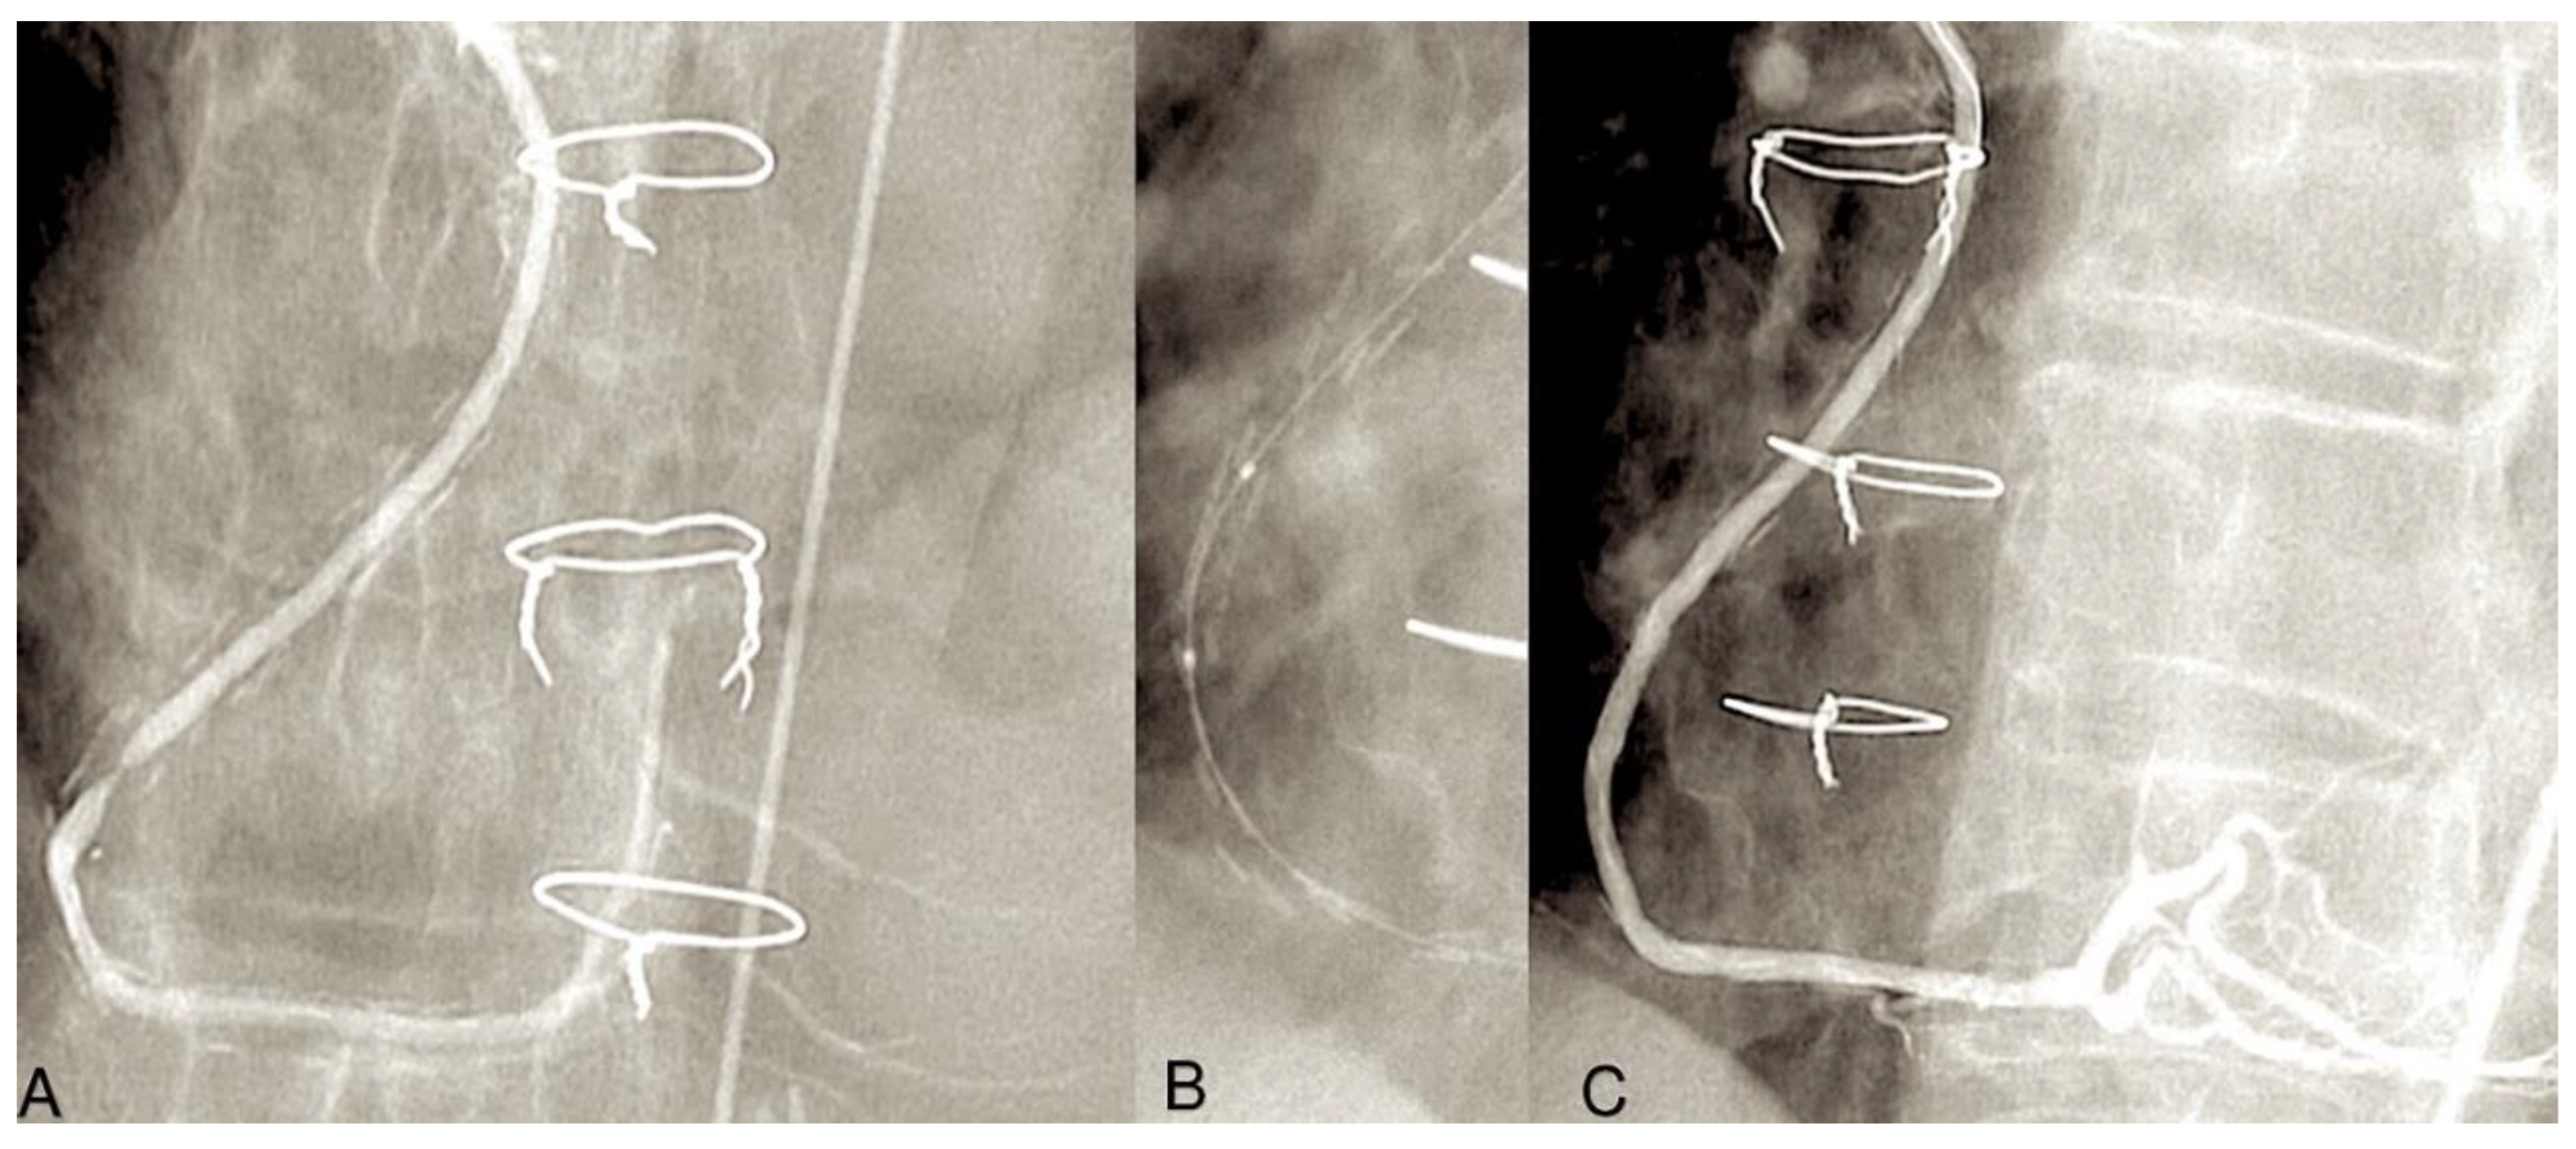

- Schwann TA, Zacharias A, Riordan CJ, Durham SJ, Shah AS, Habib RH. Sequential radial artery grafts for multivessel coronary artery bypass graft surgery: 10-year survival and angiography results. Ann Thorac Surg 2009. 88:31-9. [CrossRef]